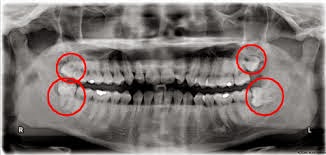

While protecting the appearance of your teeth may be the most obvious reason to prevent and treat dental abrasion, weakened enamel can also contribute to more serious dental problems over time. Many patients experience increased tooth sensitivity to heat and cold. In addition, without its protective outer layer, a tooth may be more susceptible to infection. In advanced cases, when dental abrasion is left un diagnosed and/or untreated, a tooth may need a tooth filling or tooth extraction.

If any portion of your tooth surface has begun to wear away, your dentist may be able to correct the problem with fluoride treatment. Depending on your needs, he or she may also use dental bonding or dental fillings to replace the lost tooth structure. Also be sure to ask your dentist about air abrasion, which is the newest method of cleaning out tooth decay -- while also relieving dental anxiety.